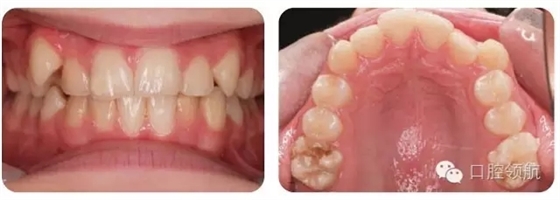

圖2.9中明顯的牙列異常有哪些?

雙側(cè)下頜側(cè)切牙和尖牙移位。

圖2.9